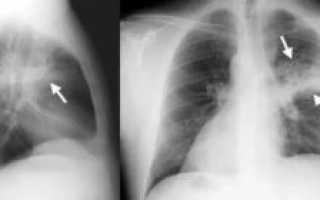

Крупозный или долевой вид пневмонии характеризуется большими потемнениями средней интенсивности, поражающими одну или обе доли лёгких.

Выделяют следующие признаки, видимые при расшифровке снимков:

- тени на одной или двух сторонах;

- смещение пространства среднего отдела грудной клетки к области воспаления;

- сильная деформация рисунка лёгких;

- заполнение лёгочного пространства жидкостью;

- изменение куполов диафрагмы;

- расширенные корни лёгких.

Для точной диагностики крупозного воспаления проводят прямую и боковую рентгенографию для оценки тяжести поражения лёгочных долей.

На фото видны признаки пневмонии:

- светлые полости;

- размытые контуры воспалительных очагов;

- затемнения за счёт уплотнений.

Сравнение здоровых и воспаленных легких на рентгенографии Абсцесс лёгких на рентгеновском снимке Абсцесс при левостороннем верхнедолевом воспалении лёгких Очаговая пневмония Крупозная пневмония на рентгене Казеозная пневмония